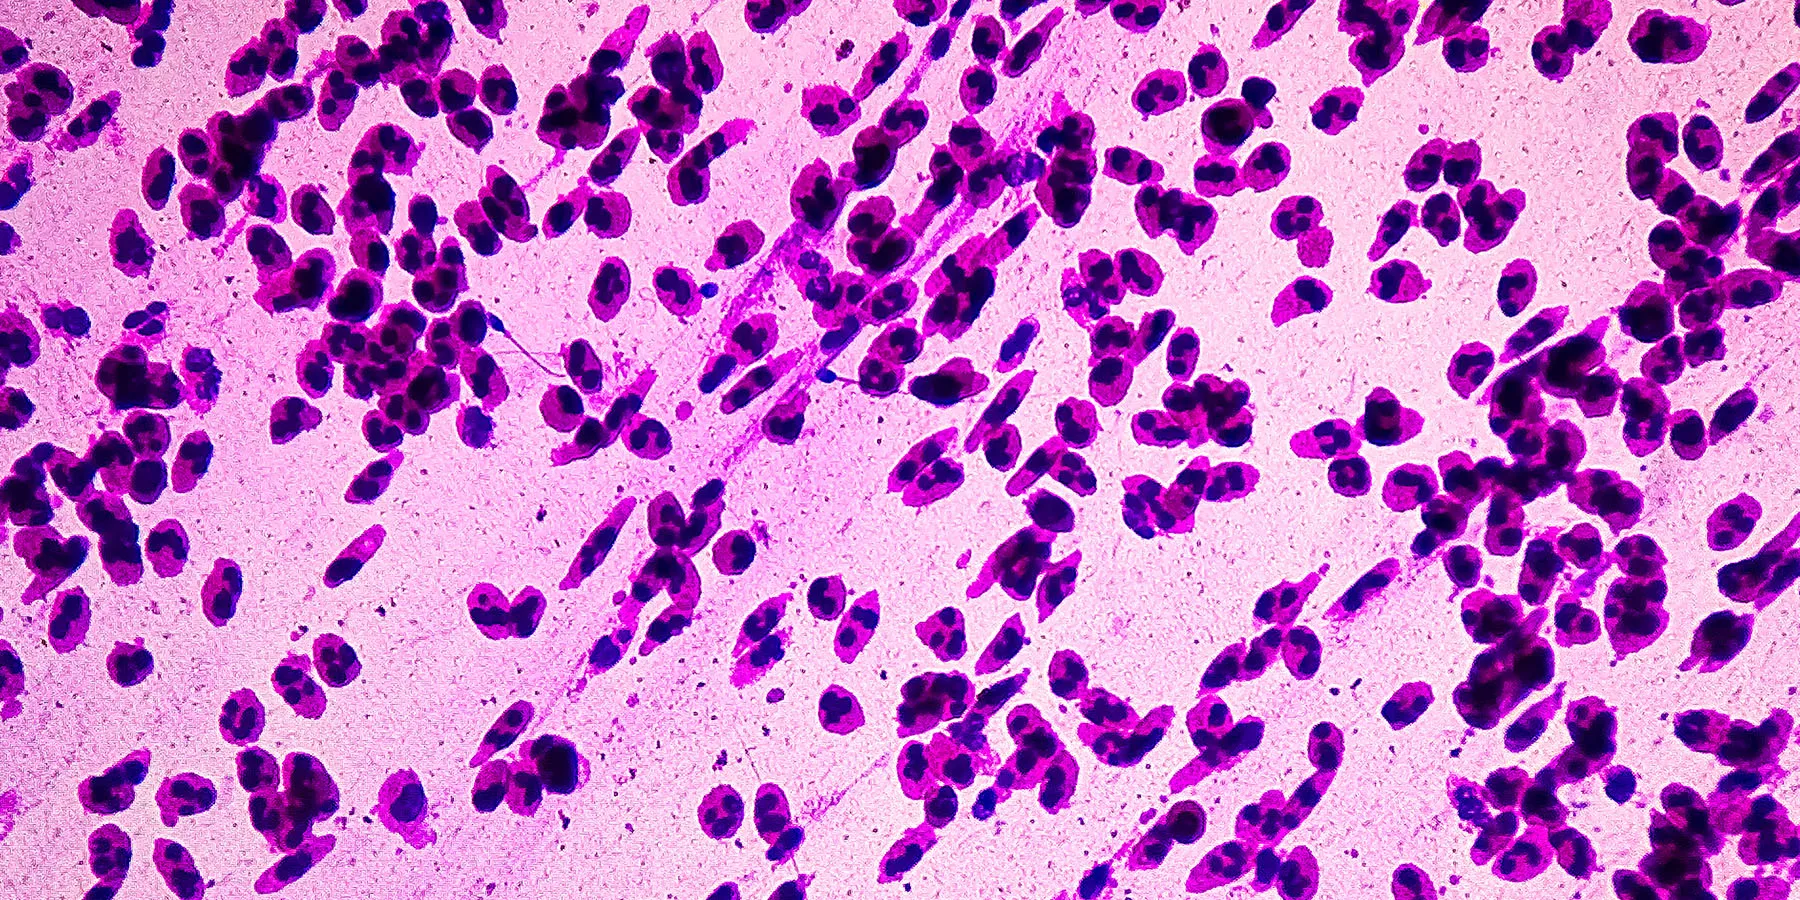

Dr. Amanda Lumsden, lead researcher, noted that ovarian cancer is often diagnosed late, leading to a five-year survival rate of less than 30 percent. Early detection dramatically improves survival, making understanding risk factors critical. The study also found that factors like giving birth to two or more children, lower body weight, and certain biomarkers in the blood were associated with a lower risk.